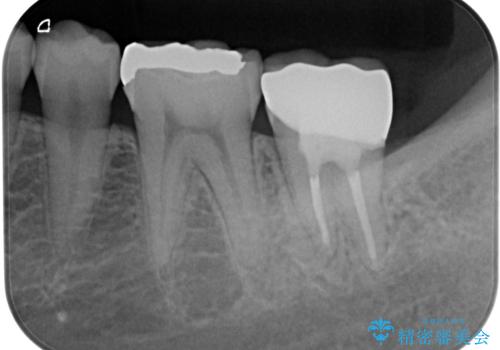

その後、歯根だけとなっている歯はインプラントに、神経組織の失活している歯は根管治療を行い、いずれもオールセラミッククラウンにて補綴治療を行うこととしました。

右上のインプラント治療は、1DAYインプラント治療(抜歯即時埋入・即時荷重)の適応となりましたので、通常3回必要な外科処置の回数を1回に集約させることができました。

口腔内の環境が大きく改善し、現在はご自身のプラークコントロールにより良い状態が維持できるようになりました。